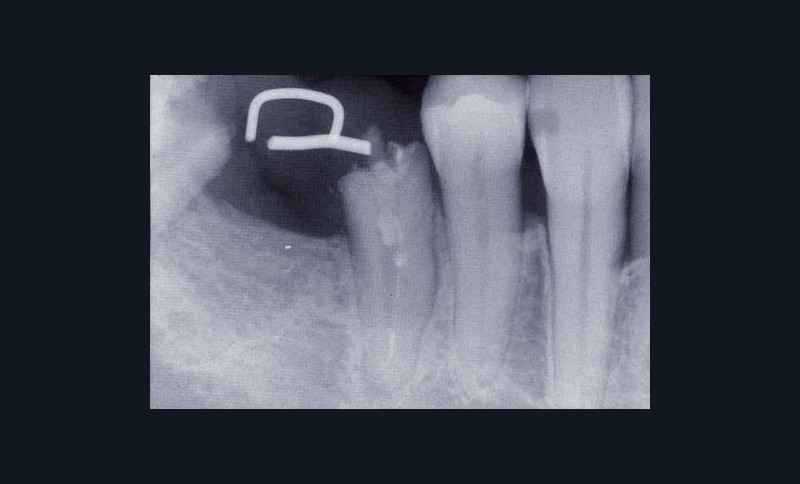

Une patiente âgée de 45 ans consulte à la fin des années 1990 avec une contention en échelle au maxillaire afin de soulager les mobilités des dents antérieures.

Les examens cliniques et radiographiques montrent une parodontite chronique généralisée (fig. 1a à m).

La patiente, en bonne santé, ne fume pas.

Nous décidons d’entreprendre une thérapeutique initiale parodontale classique dans tous les secteurs, y compris l’extraction de 24, un bridge de 45 à 48 avec 46 en pontique, un bridge complet de contention de 17 à 27 sur 11 piliers dentaires et une greffe épithélio-conjonctive sur 31. Cette dernière ne sera jamais réalisée. Le bridge maxillaire permettra de réduire le surplomb antérieur et d’améliorer le sourire de la patiente, ce qui constitue l’une de ses demandes.